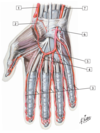

1 - Abductor pollicis brevis muscle

1 - Flexor pollicis brevis muscle

1 - Opponens pollicis muscle

1 - Adductor pollicis muscle

1 - Abductor digiti minimi muscle

1 - Flexor digiti minimi brevis muscle

1 - Opponens digiti minimi muscle

1 - lumbrical muscles 1 and 2

2 - lumbrical muscles 3 and 4

1 - Dorsal interosseous muscles

1 - Palmar interosseous muscles